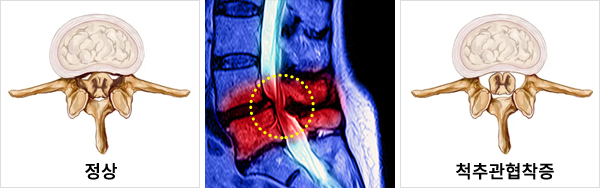

신경이 지나가는 통로인 척추관이 좁아지면서

신경이 눌려 통증이 발생하는 질환입니다.

주로 40~50대에 발병률이 높은 질환으로 나이가 들면서

뼈와 인대, 근육 등이 두꺼워지면서 척추관이 좁아져 신경을 압박하여 발생하는데,

드물지만 선천적으로 척추관이 좁은 경우도 있습니다.

고령화 사회가 되면서 척추관 협착증 환자가 늘어나고 있는 추세로

허리를 많이 쓰는 직업, 무리한 운동, 좌식생활 등이

그 원인으로 지목되고 있습니다.